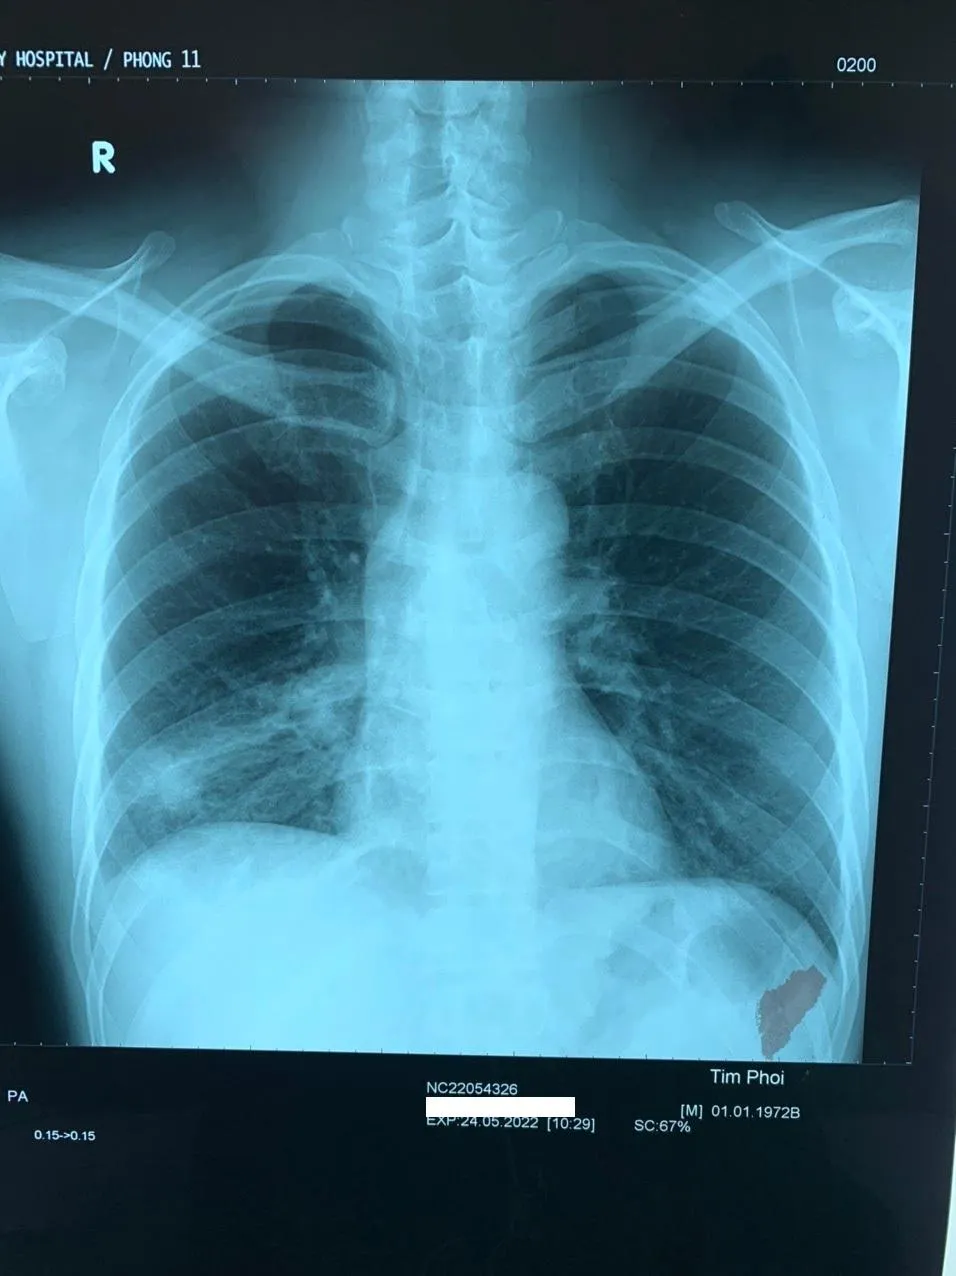

Bệnh nhân là nam (50 tuổi, quê Kiên Giang) kể: Cách đây 20 năm bị sặc một mảnh xương vào đường thở, nhưng khi đi khám ở tuyến y tế cơ sở thì chụp X-quang không thấy dị vật.

Tuy nhiên, sau đó bệnh nhân về bị ho ra máu, khạc đàm mủ kéo dài. Dù đi nhiều cơ sở y tế và chụp X-quang phổi nhưng không nơi nào thấy được mảnh xương.

Trực tiếp gắp dị vật ra, BS Vân Thanh mô tả mảnh xương nằm 20 năm trong phổi nên xung quanh mọc rất nhiều mô hạt, mảnh xương sắc nhọn cắm vào thành phế quản sâu. Do vị trí nằm khuất sau bóng tim nên các kết quả chụp X-quang không thấy là điều dễ hiểu.